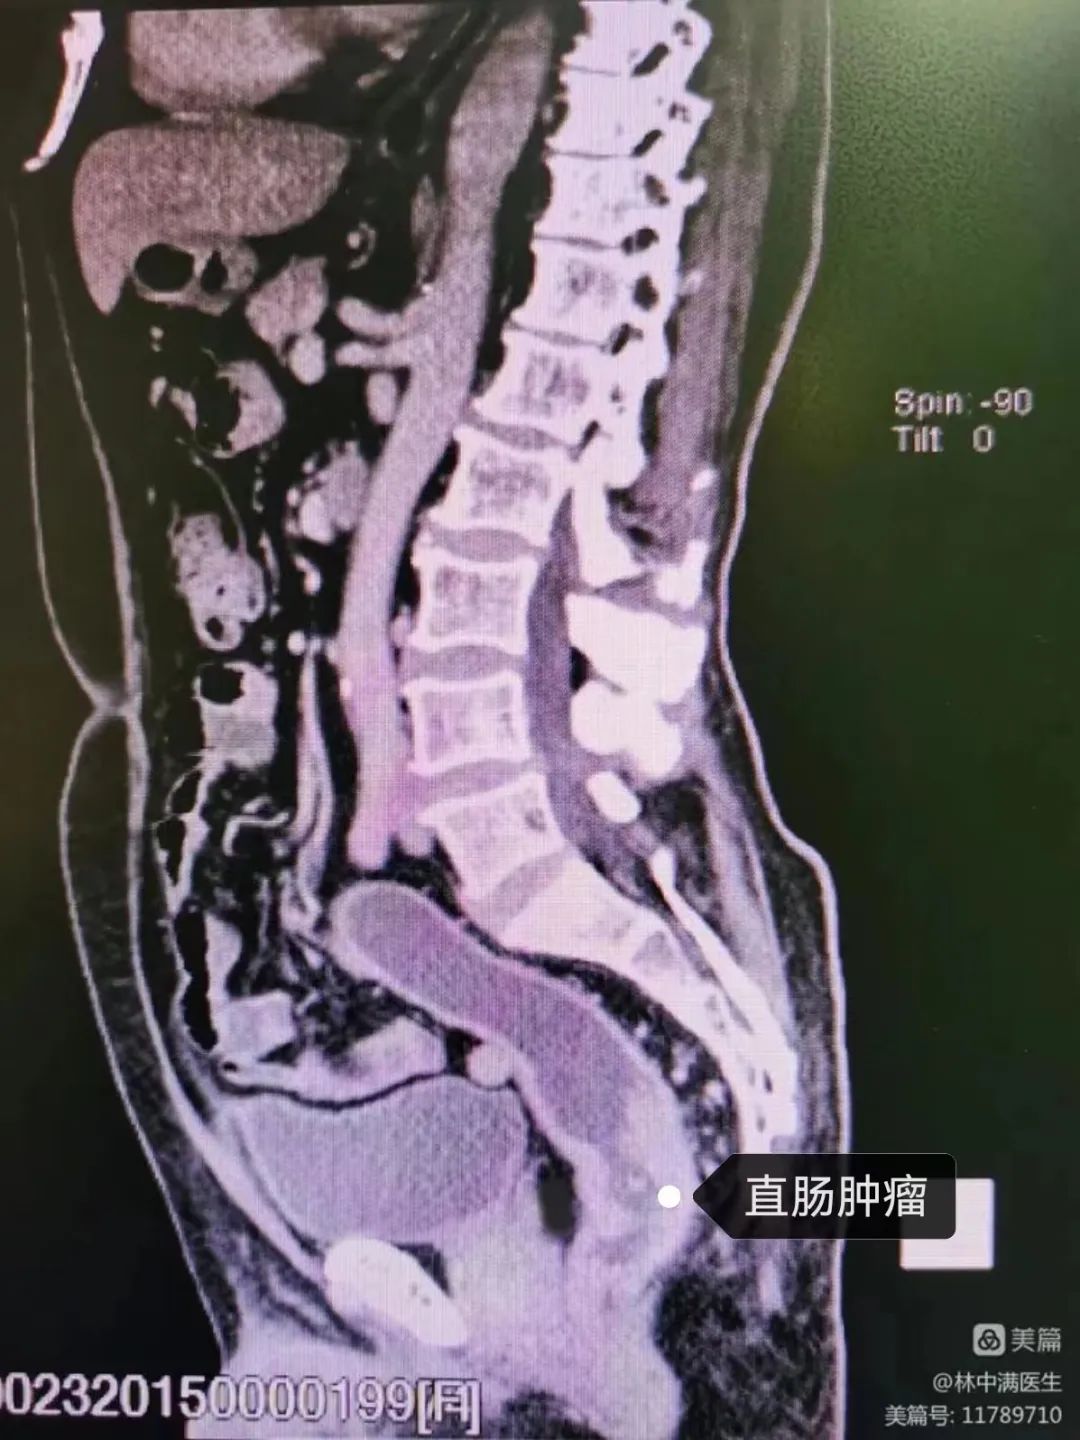

CT三维提示肿瘤位置

接下来几天,陈医生每天查房都亲切地称其老师,并主动向科室人员介绍该患者是他的高中老师。经过陈医生细致全面的检查确诊为,直肠癌,距离肛门4cm,属于临床的超低位直肠癌。并汇报组长林中满副主任医师、科主任吴惠慈主任,最终讨论确定了手术方案,手术难度大,保肛存在困难,但将尽全力争取保留

经询问采集病史,我们了解到,原来老师本次住院是因为反复便血1年了。经过门诊检查考虑是直肠占位,才住院治疗。